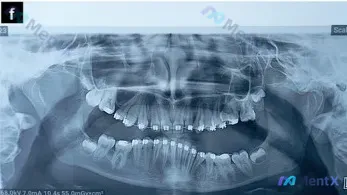

正畸治疗中的13岁全景片,除了阻生智齿还需关注什么?

整理了一份13.11岁患者的全景牙齿X光片资料,目前患者处于正畸治疗中,先放核心的影像学发现,大家看看第一眼的评估优先级会怎么排?

- 恒牙列,全口可见正畸托槽与弓丝

- 双侧上颌第三磨牙已萌出,双侧下颌第三磨牙(38、48)呈近中阻生

- 下颌左侧第一磨牙(36)区域缺失

- 颌骨轮廓基本连续,未见明显骨质破坏或根尖周低密度透射影

📋答案:基于临床优先级排序:1. 双侧下颌第三磨牙近中阻生及其对邻牙的潜在风险;2. 正畸治疗中的牙根吸收监测与牙槽骨改建评估;3. 下颌左侧第一磨牙缺失间隙的处理状态确认。目前无明确病理性改变征象。